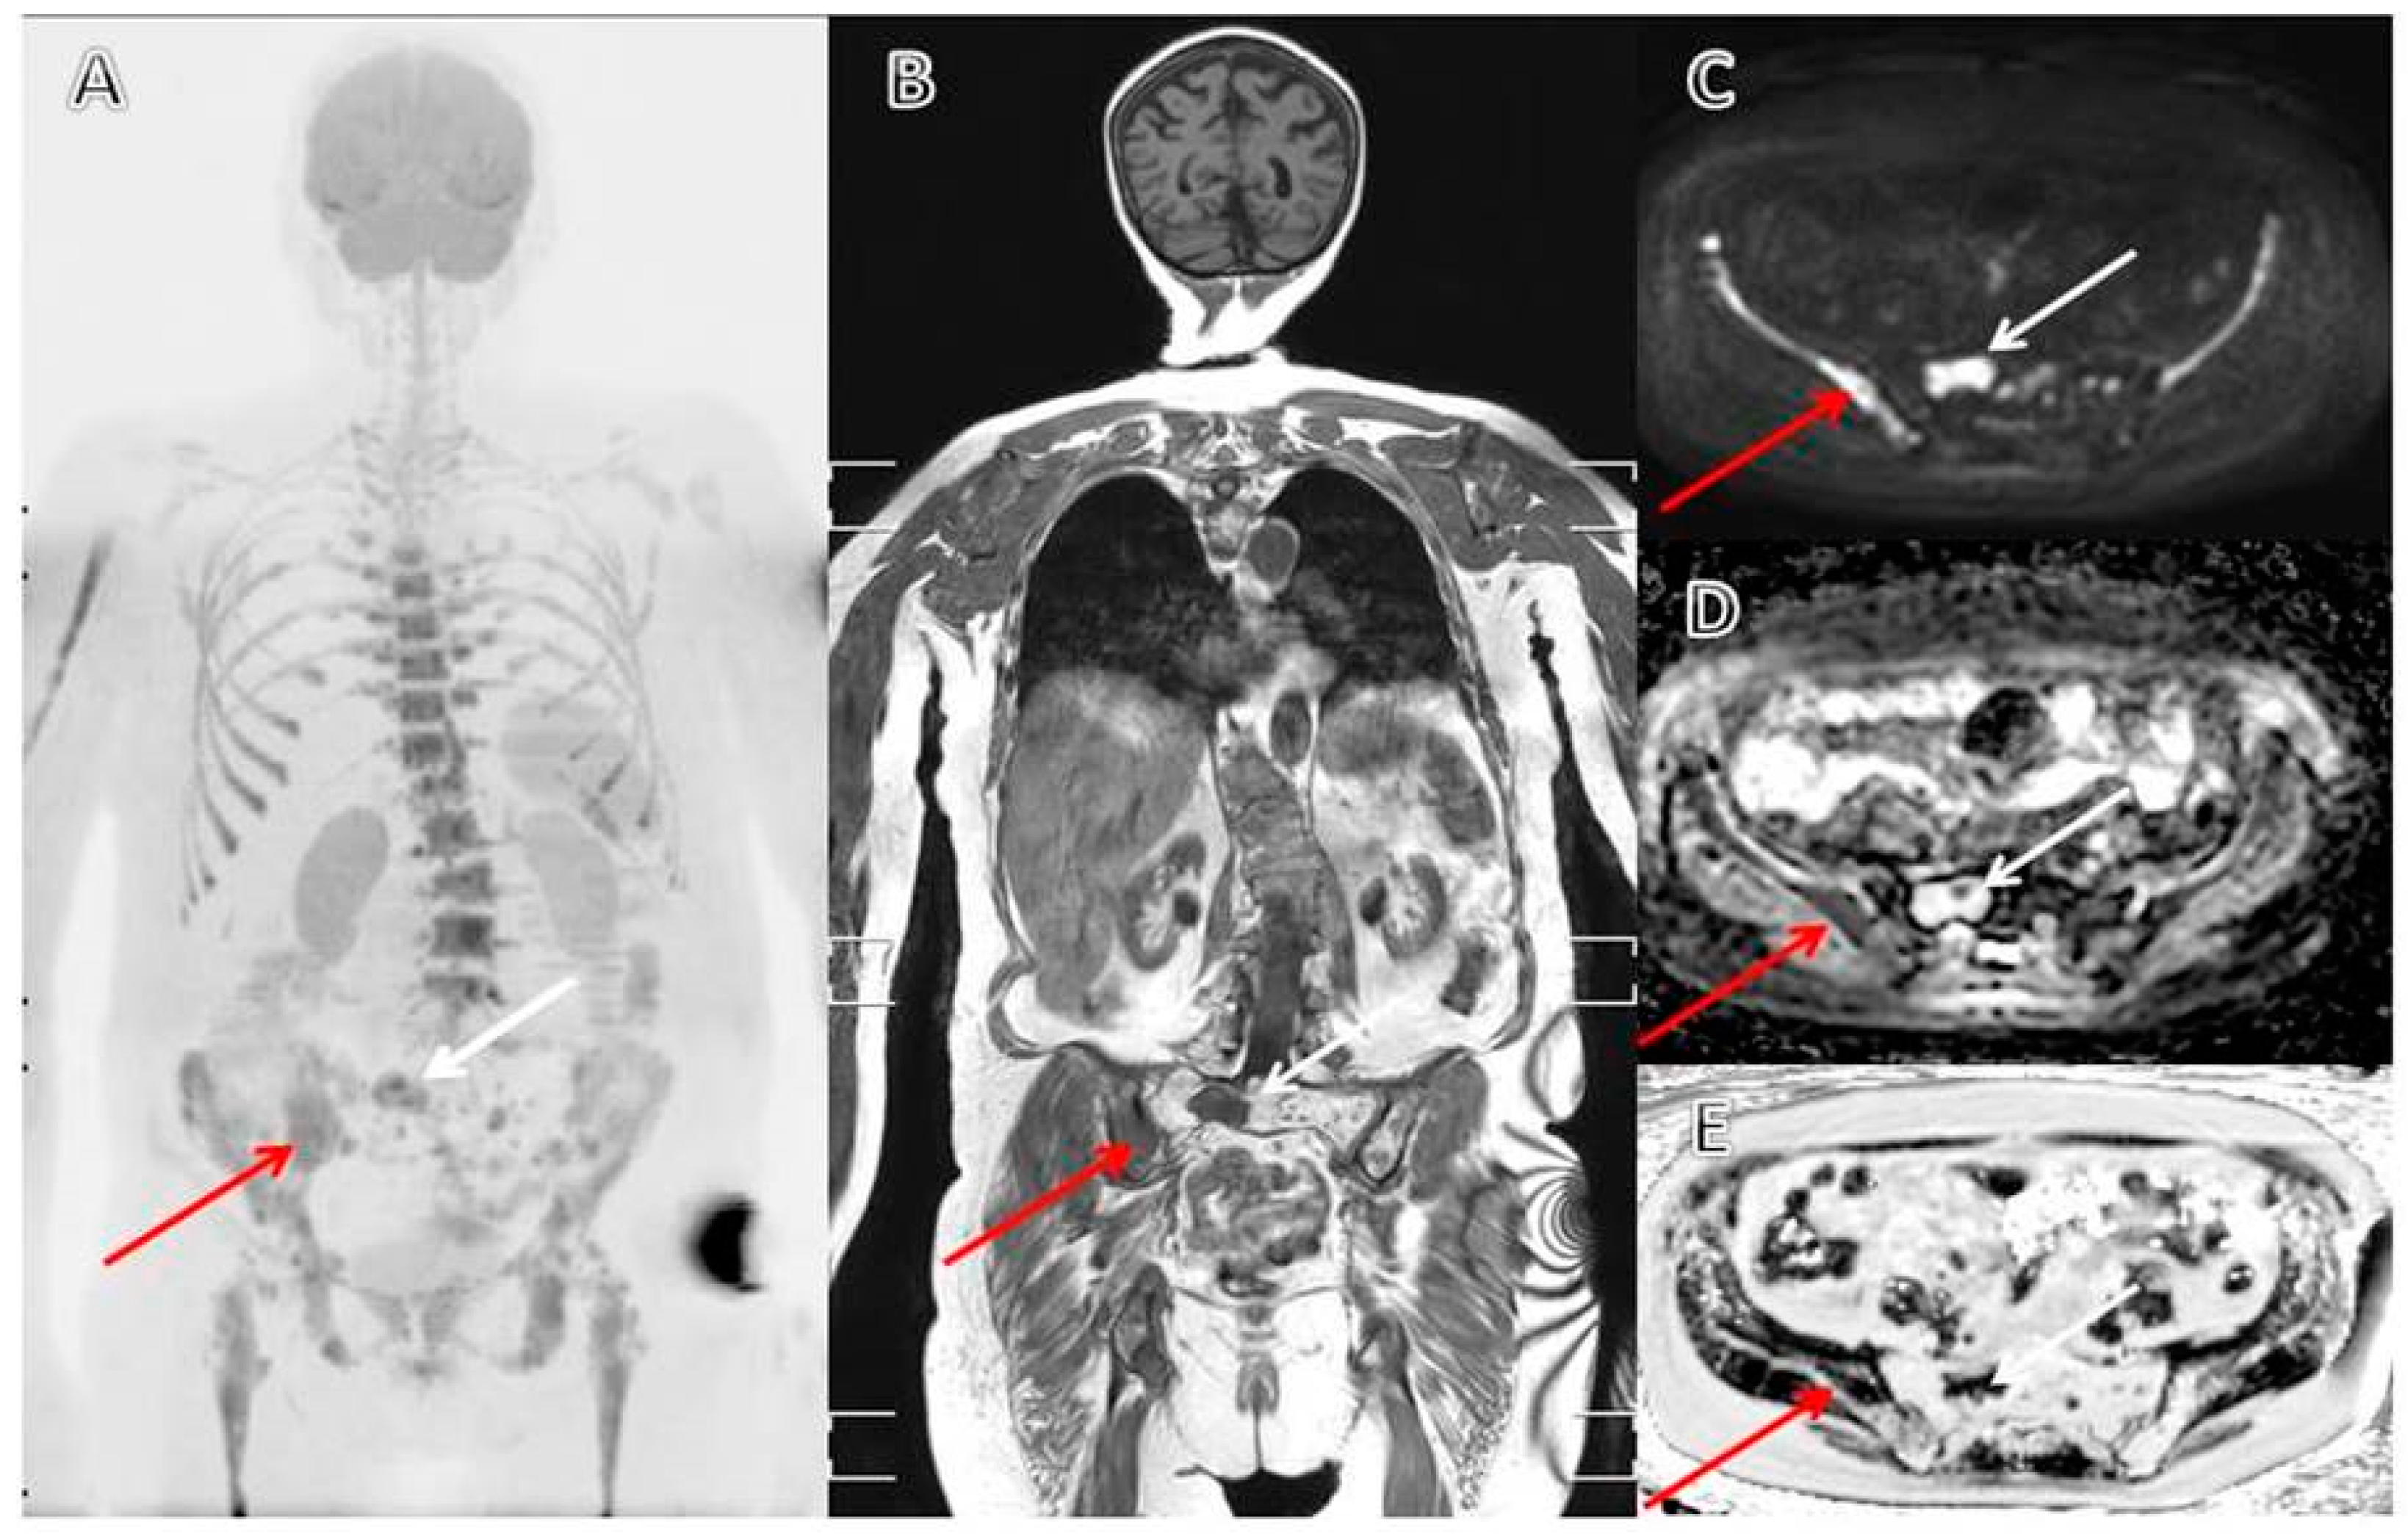

- Moreau, P.; Attal, M.; Caillot, D.; Macro, M.; Karlin, L.; Garderet, L.; Facon, T.; Benboubker, L.; Escoffre-Barbe, M.; Stoppa, A.-M.; et al. Prospective Evaluation of Magnetic Resonance Imaging and [18F]Fluorodeoxyglucose Positron Emission Tomography-Computed Tomography at Diagnosis and Before Maintenance Therapy in Symptomatic Patients With Multiple Myeloma Included in the IFM/DFCI 2009 Trial: Results of the IMAJEM Study. J. Clin. Oncol. 2017, 35, 2911–2918. [Google Scholar] [PubMed]

- Pawlyn, C.; Fowkes, L.; Otero, S.; Jones, J.R.; Boyd, K.D.; Davies, F.E.; Morgan, G.J.; Collins, D.J.; Sharma, B.; Riddell, A.; et al. Whole-body diffusion-weighted MRI: A new gold standard for assessing disease burden in patients with multiple myeloma? Leukemia 2016, 30, 1446–1448. [Google Scholar] [CrossRef] [PubMed]